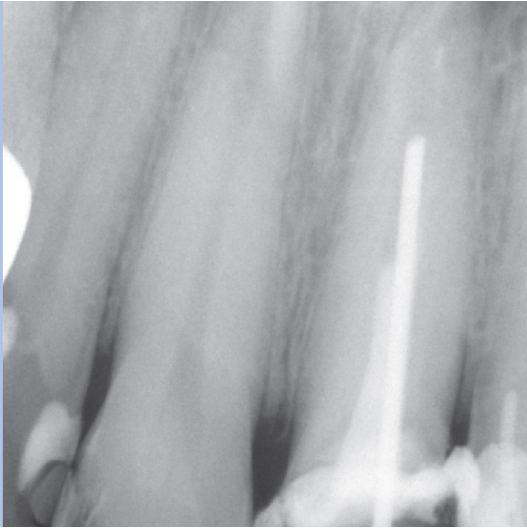

Before

After

Before Root Canal treatment

After Root Canal treatment